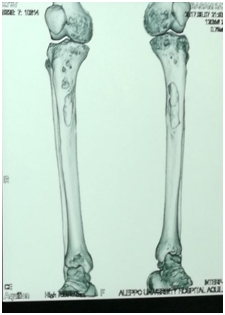

Chest Multi-Slice CTscan revealed several diffused interstitial reticular densities in both pulmonary fields with small nodular densities without enlargement of lymphatic nodes (Figure 3). Pelvis Multi-Slice CT scan revealed lytic lesions in hip and legs without invasion of adjacent tissues (Figure 4). We sent the Bronchial incisional biopsy taken by bronchoscopy and surgical incisional biopsy taken from left tibia to pathology department.

Figure 4 Pelvis Multi-Slice CT scan revealed lytic lesions in hip and legs without invasion of adjacent tissues.

There is bone involvement in 78% of patients with LCH. Bone involvement is usually in the flat bones, with lesions of the skull, pelvis, and ribs accounting for more than 50% of all lesions. The lesions can be painful or asymptomatic.4 In our case, the patient presented with pain and edema in both legs and inability to walk.

Radiographic features in bone LCH depends on site of involvement and phase of the disease. X-ray of the pelvic and legs showed lytic lesions. MS-CT scan of the pelvic and legs showed several generalized lytic lesions without infiltration to the near tissues. The biopsy from tibia confirmed LCH diagnosis.